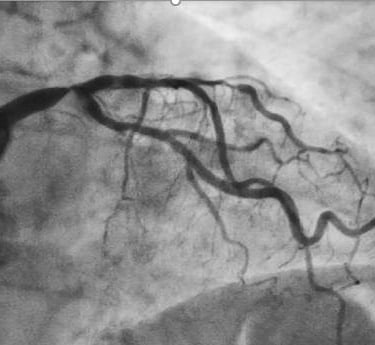

O diagnóstico de doença coronariana no tronco da coronária esquerda (TCE) pode causar preocupação, mas é importante saber que existem tratamentos modernos e eficazes disponíveis. Este texto visa esclarecer suas dúvidas sobre o tratamento percutâneo (angioplastia), uma opção terapêutica que tem mostrado excelentes resultados em casos selecionados

O tronco da coronária esquerda é um vaso sanguíneo crucial que fornece aproximadamente 75% do sangue para o coração. Quando existe obstrução significativa neste vaso, o tratamento adequado é fundamental para preservar a vida e qualidade de vida do paciente.

1. Ultrassom Intracoronário (USIC/IVUS)

- Permite visualização detalhada da lesão

- Auxilia na escolha do tamanho ideal do stent

- Confirma o posicionamento adequado do stent

- Aumenta a segurança e eficácia do procedimento